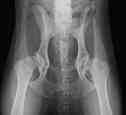

| Vom

Wellensittich bis zum Bernhardiner - vom Zahn bis zur Hüfte

können und müssen scharfe

und kontrastreiche

"Standbilder" angefertigt werden. |

| Zugelassene

Röntgenstelle für HD

(Hüftgelenksdysplasie), ED

(Ellenbogengelenksdysplaie) und OCD

(Osteochondrosis dissecans). |